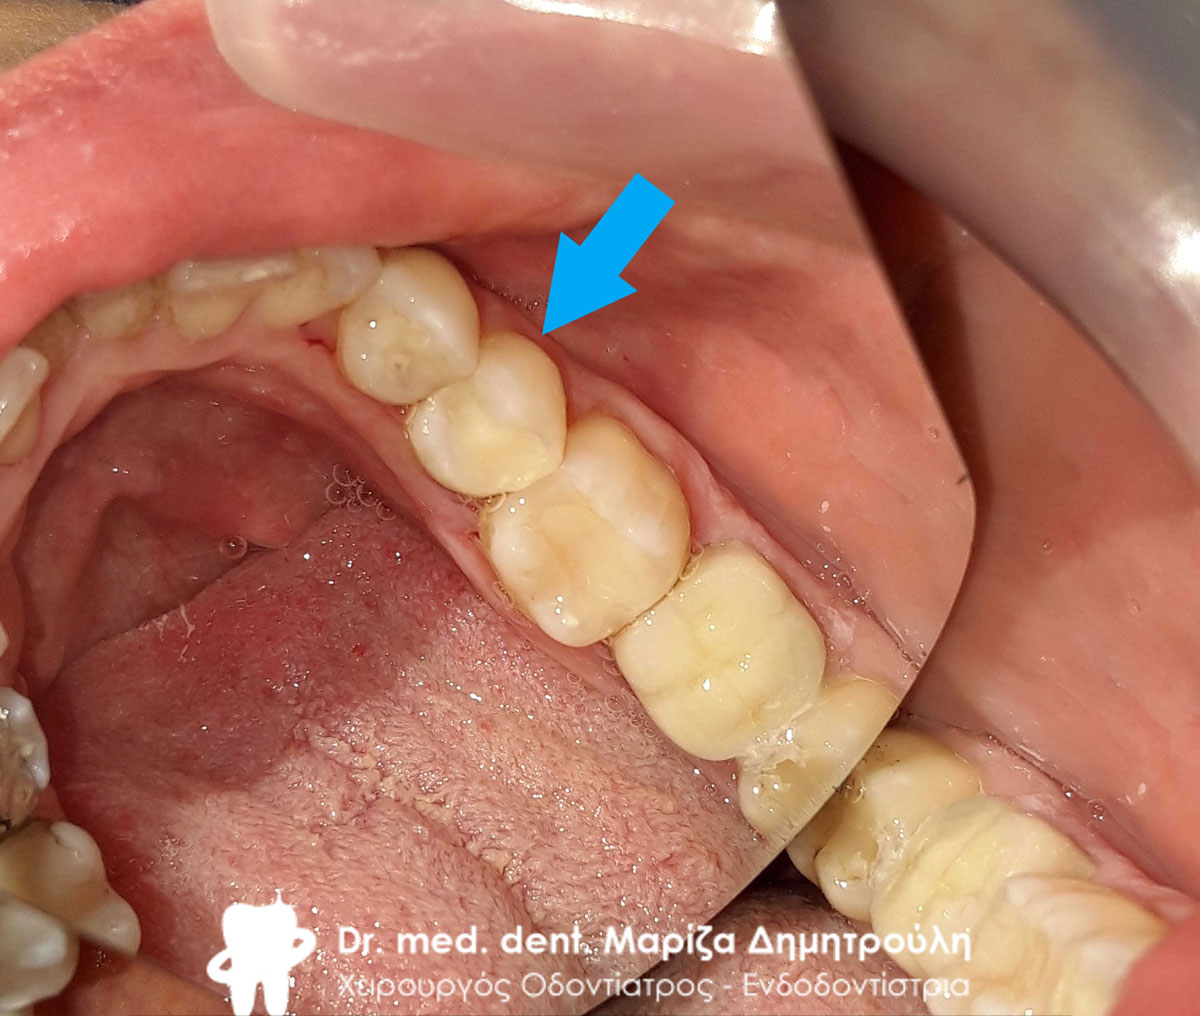

Τελική εικόνα του ολοκεραμικού πέταλου ζιρκονίου στην κάτω γνάθο

Τελική εικόνα του ολοκεραμικού πέταλου ζιρκονίου στην κάτω γνάθο

Τελική εικόνα της ολοκεραμικής γέφυρας ζιρκονίου στην κάτω γνάθο

Τελική εικόνα της ολοκεραμικής γέφυρας ζιρκονίου στην κάτω γνάθο

Τελική εικόνα της ολοκεραμικής γέφυρας ζιρκονίου

Τελική εικόνα της ολοκεραμικής γέφυρας ζιρκονίου

Τελική εικόνα της ολοκεραμικής γέφυρας ζιρκονίου